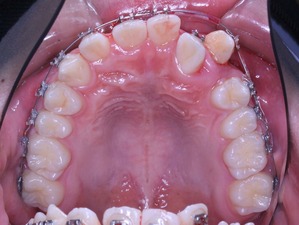

上からみてみるとどうでしょうか?

もう少し犬歯が後方に移動してもらえると、2番目の歯が前方に移動可能な感じです